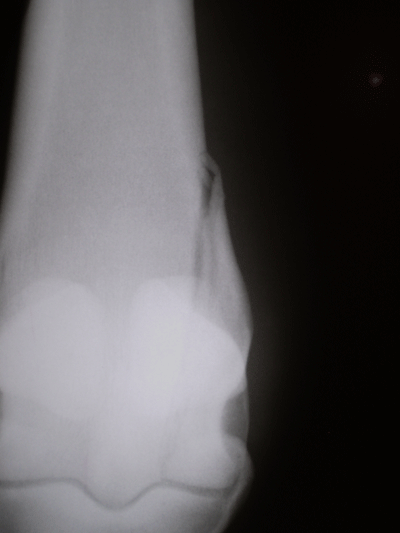

CIRURGIAS

Cirurgias abdominais, de tecido mole, ortopédicas, incluindo vídeo-artroscopia e  reparo de fratura em ossos longos

EXAMES DE IMAGEM

Ultrassonografias em geral, radiologia digital, endoscopia em estação e dinâmica (durante exercício) e gastroscopia